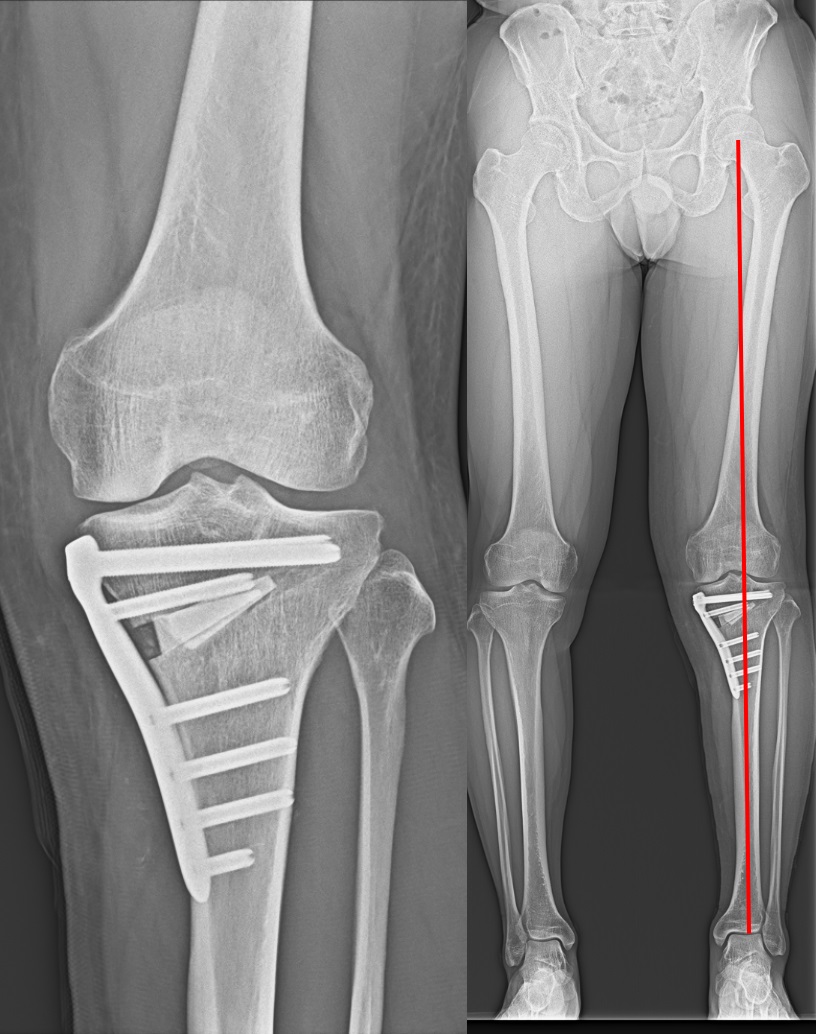

高位脛骨骨切り術(high tibial osteotomy: HTO)

初期の変形性膝関節症や大腿骨顆骨壊死などに適応があります。

O脚変形のために内側に偏った荷重線を、自分の骨を骨折させ角度を変えることにより、比較的きれいな軟骨の存在する外側に荷重線を移動させる手術です。荷重線が移動することによって膝の痛みが緩和されます。

膝関節そのものは温存されるため、人工膝関節置換術では困難な正座やスポーツ活動へ復帰された患者さんが多くいらっしゃいます。